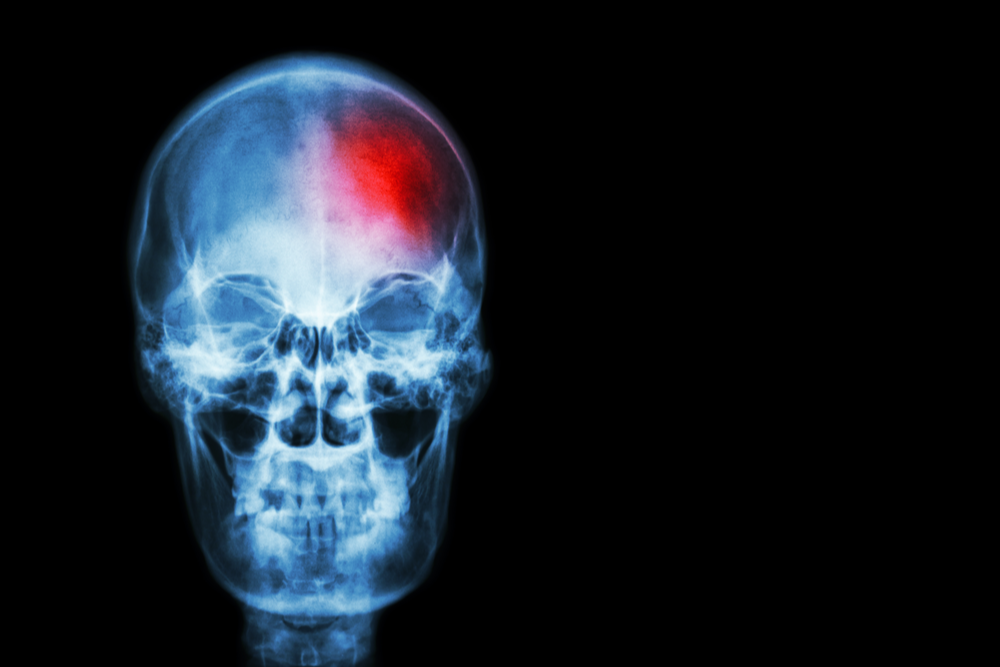

Инсульт – одно из самых серьезных заболеваний, наиболее часто приводящих к грозным последствиям и инвалидности. Однако существуют простые методы профилактики инсульта, и практически каждый человек в силах применять их.